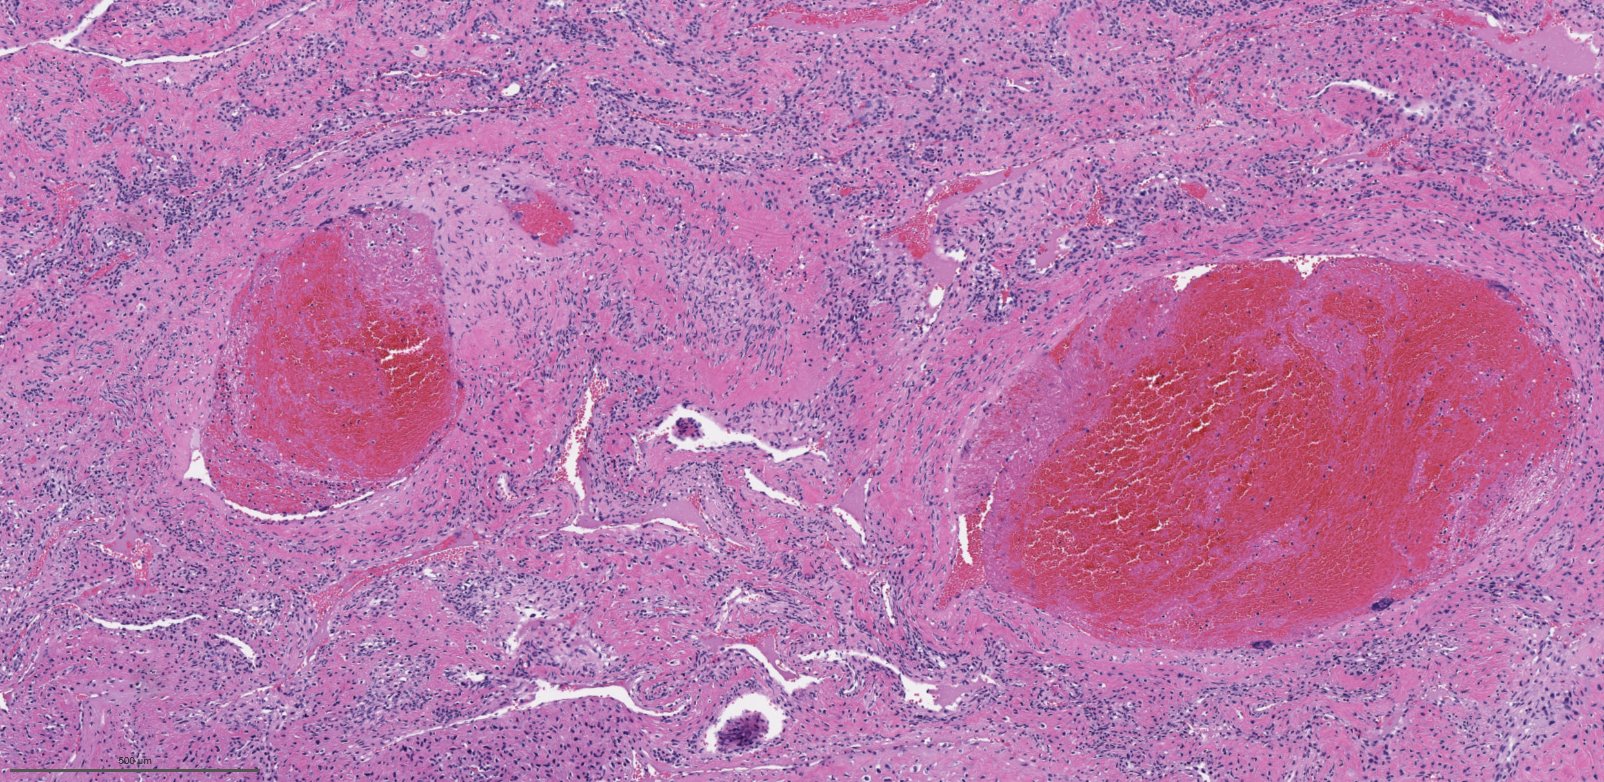

Microscopic (histologic) description

- Benign fibrovascular lesion composed of 2 components

- Vascular space of various sizes, ranging from dilated branching vessel of various thickness to slit-like capillaries

- Fibrous or collagenous stroma with fibroblasts

- Central area of the tumor is typically cellular, composed of fibroblasts or myofibroblasts with spindle, round or stellate morphology

- Stroma can be fibrous, edematous or collagenized

- Fibrinous thrombi may be seen in dilated vessels

- Frequently contain (abundant) mast cells

- Mitotic figures are usually absent

Microscopic (histologic) images

Contributed by Bin Xu, M.D., Ph.D.

Contributed by Kelly Magliocca, D.D.S., M.P.H.